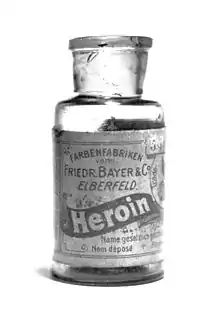

La heroína fue sintetizada por primera vez por Charles Romley Alder Wright a finales del siglo XIX, que consiguió aislarla gracias a la acetilación del clorhidrato de morfina, un producto obtenido de la adormidera. «Heroína» fue el nombre comercial que la empresa Bayer puso a la nueva sustancia, que la lanzó al mercado como sustituta de la morfina, creyéndola menos adictiva. A nivel internacional, la heroína está controlada por las Listas I y IV de la Convención Única sobre Estupefacientes y por lo general es ilegal su fabricación, posesión y venta sin licencia.[7] Producida sobre todo en Afganistán y Birmania, está íntimamente unida al tráfico internacional de drogas y ha sido responsable de epidemias severas en varios países de Occidente durante el siglo XX. Afganistán produjo el 95 % del opio del mundo en 2012,[8] y el 66 % en 2015,[9] manteniéndose como el principal productor mundial de opio en las últimas dos décadas. Se ha registrado un aumento significativo de la oferta y la demanda a nivel mundial en los últimos años;[10] en países como Estados Unidos el consumo de heroína se ha multiplicado en la segunda década del siglo XXI hasta convertirse en una verdadera epidemia (ver Fentanilo).[11][12]

Etimología

En 1895, la compañía farmacéutica alemana Bayer comercializaba diacetilmorfina como uno más de sus productos bajo receta médica con el nombre comercial de Heroína.[13] El nombre fue registrado en junio de 1898 y deriva del alemán la palabra heroisch (que quiere decir, heroica), debido a sus efectos «heroicos» (efectos beneficiosos, y de alivio de la tos) y el sufijo medicinal -in (-ina) (como en koffein / cafeína), con lo que se creó a la vez la connotación muy vendible de la Femme Héroïne (Alemania en esa época era muy francófila).[13] Se desarrolló principalmente como un sustituto de la morfina, supresor de la tos «que no crea adicción ni otros efectos secundarios». La morfina en ese momento era una droga recreativa popular, y Bayer deseaba encontrar una similar, pero que no creara tanta adicción. Aunque la publicidad de Bayer la presentaba como un "sustituto no adictivo de la morfina", la heroína pronto generaría una de las mayores tasas de dependencia entre sus usuarios, superando a la morfina.[14]

Historia

En 1874, Charles Romley Alder Wright aisló un opiáceo nuevo gracias a la acetilación del clorhidrato de morfina,[15] con lo cual obtuvo diacetilmorfina. El invento de Wright no se popularizó inmediatamente y la diamorfina no comenzaría a ser conocida hasta 23 años después, cuando fue re-sintetizada de forma independiente por otro químico, Felix Hoffmann.[16] Hoffmann trabajaba para la compañía farmacéutica Bayer en Wuppertal (Alemania) y su supervisor, Heinrich Dreser, lo había instado a que acetilase morfina para producir codeína, un constituyente de la adormidera y farmacológicamente similar a la morfina, pero mucho menos potente y adictiva. Sin embargo, el experimento produjo una morfina acetilada entre un 50% y un 100% más potente que la morfina. Aunque los investigadores de Bayer no fueron los primeros en producir heroína, si le dieron su nombre y fueron pioneros en su fabricación industrial y comercialización,[17] que comenzó en 1898, pocos días después de sacar a la venta la aspirina. Se cree que el nombre de heroína se deriva de la palabra «heroica».[18]

El fármaco fue comercializado entre 1898 y 1910 como un sedante para la tos y como sustituto de la morfina pensando que era menos adictiva. Esto se vio facilitado por el hecho de que se creía que la heroína, producía algo menos de euforia con desviaciones mínimas en el comportamiento y la inteligencia, suponiendo un uso breve. En su 11.ª edición de 1910, la Enciclopedia Británica, en su artículo sobre los estados de la morfina afirmaba: